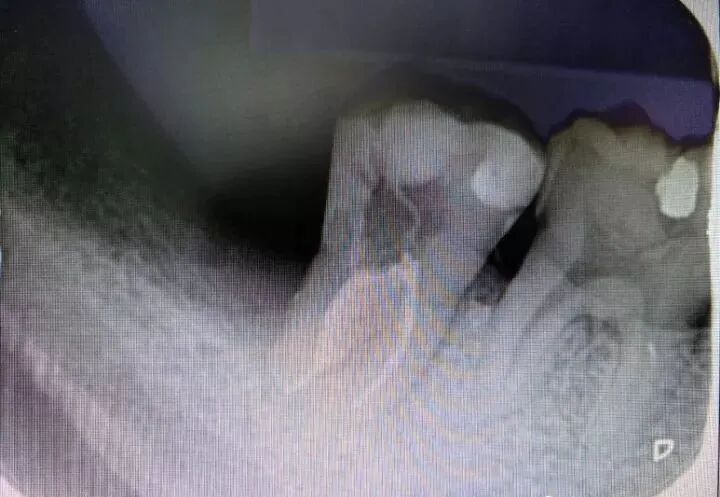

图9 47初诊片